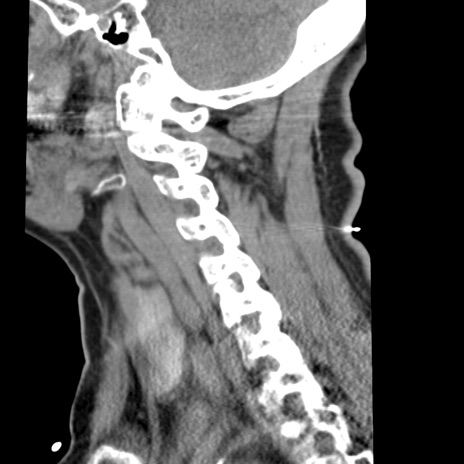

症例50 頚椎CT(矢状断像)

【症例】60歳代女性

【主訴】後頭部〜右後頸部にかけての痛み

【現病歴】本日飲食店でコーヒーを飲んでいたところ、突然後頭部〜右後頸部にかけて痛みが出現し、右上肢の感覚障害を伴ったため救急要請。

【身体所見】脳神経学的に明らかな異常所見を認めず。右上肢に軽度の感覚障害あり。

異常所見と診断は?

頚椎CT